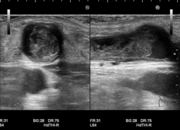

石灰化画像

吻合部画像

・吻合部の観察

吻合形態や、石灰化の有無、狭窄等を観察しています。

・静脈系の観察

吻合部から中枢へ向かって走査し、血管の走行や太さ、血管までの深さ、狭窄や石灰化、血栓等の有無を観察しています。長軸断面、短軸断面それぞれで観察し、また、カラードプラも使用しできるだけ正確に、血管内の状況を把握するようにしています。